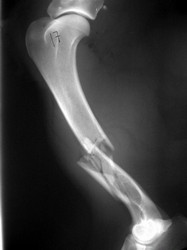

PRÁCTICAS CURSO DE FIJACIÓN EXTERNA PERFECCIONAMIENTO.

Húmero.